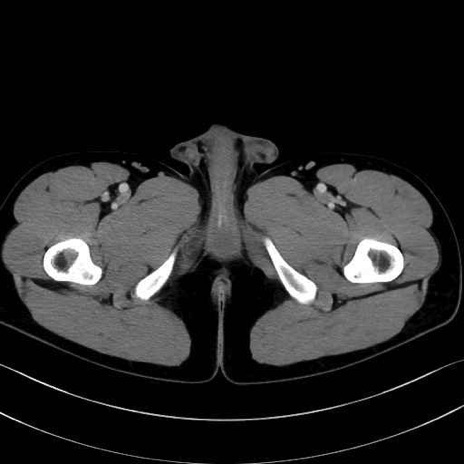

小殿筋 (Gluteus minimus)